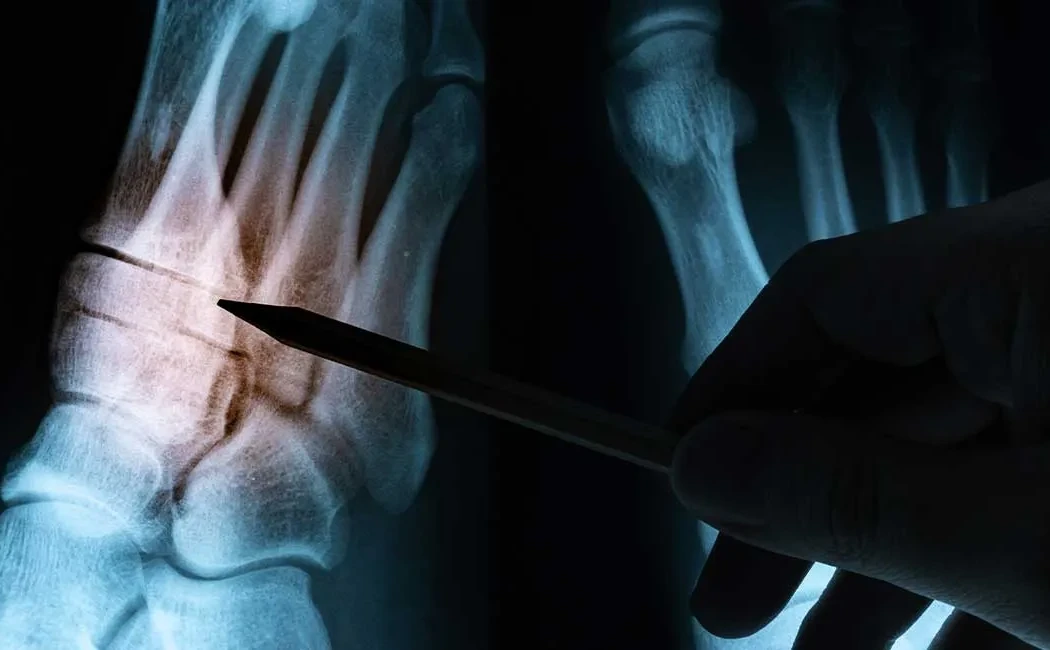

The surgery begins with comprehensive radiological evaluation. CT scans and full-length leg X-rays (orthoradiograms) precisely measure the deformity’s angle and location. The surgeon then realigns the bone using osteotomy-based deformity corrections.